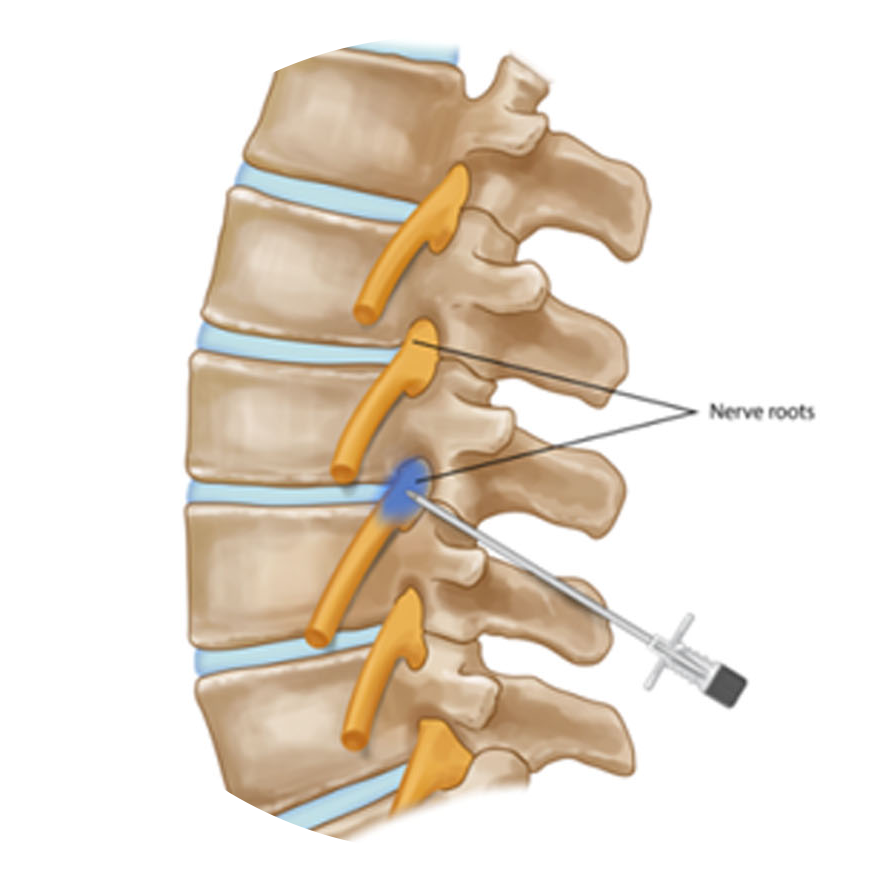

Para lidar com a dor crônica na coluna, é essencial adotar uma abordagem abrangente, que inclua técnicas cirúrgicas avançadas, intervenções minimamente invasivas e uma equipe multidisciplinar dedicada ao manejo da dor. Aliviando a dor crônica na coluna, não apenas melhoramos a função física, mas também elevamos a qualidade de vida dos pacientes.